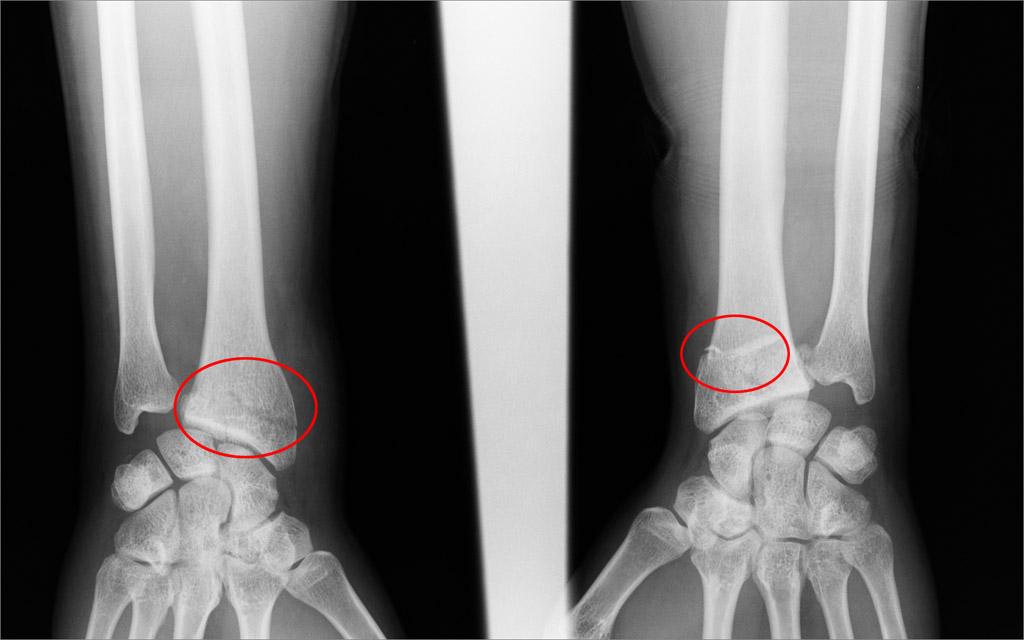

bila puknuta oba rucna zgloba, napuknuta rebra i slomljena kaciga.

http://tinyurl.com/774ezka

http://tinyurl.com/6lhn8od